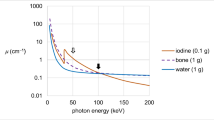

At the energy levels used in clinical routine, attenuation of biological tissues is dependent on two major interactions: Compton scattering and photoelectric effects. Compton scattering is proportional to electron density and has little energy dependence. On the other hand, the photoelectric effect is dependent on the energy of the x-ray beam (E), as well as on the atomic number (Z) of the element, and it is predominant at lower energies and near the element K-edge.

On single-energy CT platforms, the measurement of attenuation using a single x-ray spectrum does not allow for the differentiation of materials, because the attenuation coefficient is not unique. In particular, it depends either on the energy of the x-ray beam or on the concentration of a material. This means that at a given energy, a lower concentration of a higher Z material (i.e., iodine) may have the same attenuation as the higher concentration of a lower Z material (i.e., calcium). However, since materials have unique attenuation profiles at different energy levels, DECT aims to identify different elements exploiting mathematical algorithms based on their linear attenuation coefficients in order to achieve the so-called material decomposition [21,22,23].

DECT’s ability to discriminate between different materials is highly proportional to the dual-energy ratio (DEratio). Since DECT uses two different energies for measuring attenuation, DEratio is defined as the ratio of the attenuation of a given material on a low-kV dataset to the attenuation of the same material on a high-kV dataset. The energy-dependent attenuation differences of elements within a voxel allow DECT to exploit two- and three-material decomposition. The ability to differentiate the DEratio of two materials also depends on the separation between low- and high-energy spectra and the Z of the evaluated materials.

However, DECT algorithms work better when materials have high atomic numbers, because these are characterized by large differences in attenuation at different photon energies (i.e., iodine and calcium). At tube voltages used in clinical routine, it is possible to generate virtual unenhanced images by subtraction of iodine from contrast-enhanced DECT examinations or VNCa series by subtraction of calcium [5, 15, 20, 24, 25].